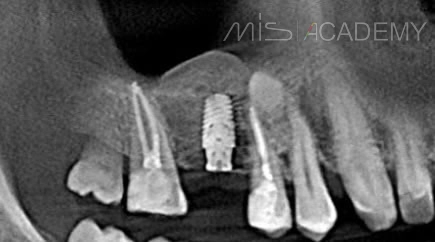

Стандартная работа в области нижней шестерки слева: - Проведена установка имплантата МИС С1 с одномоментной аугментацией ССТ и установкой формирователя десны. - Далее провизорное протезирование и постоянная...